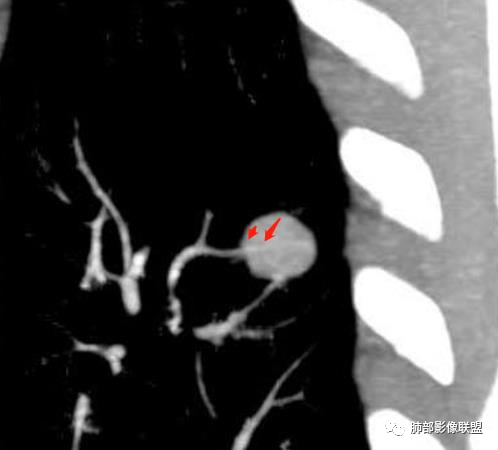

病史:男,60岁,体检左下肺结节,肿标阴性;

影像:轻微肺气肿,可能抽烟;旁边有个卫星灶4-5个,厚层无血管弯,薄层叶间裂轻度增厚,有囊腔,内侧有一个微血管,弯,另有两个微血管直,膨隆,增强血管不弯,糊墙,好像边界有些模糊,17-47-47,冠位轻度叶间裂弯。

血管进去还是比较自然

类圆形,边缘稍平直,周围晕中细微毛刺,密度均匀,均匀强化,血管走形自然,稍牵拉扭曲,支气管在近端堵塞

多发类似结节